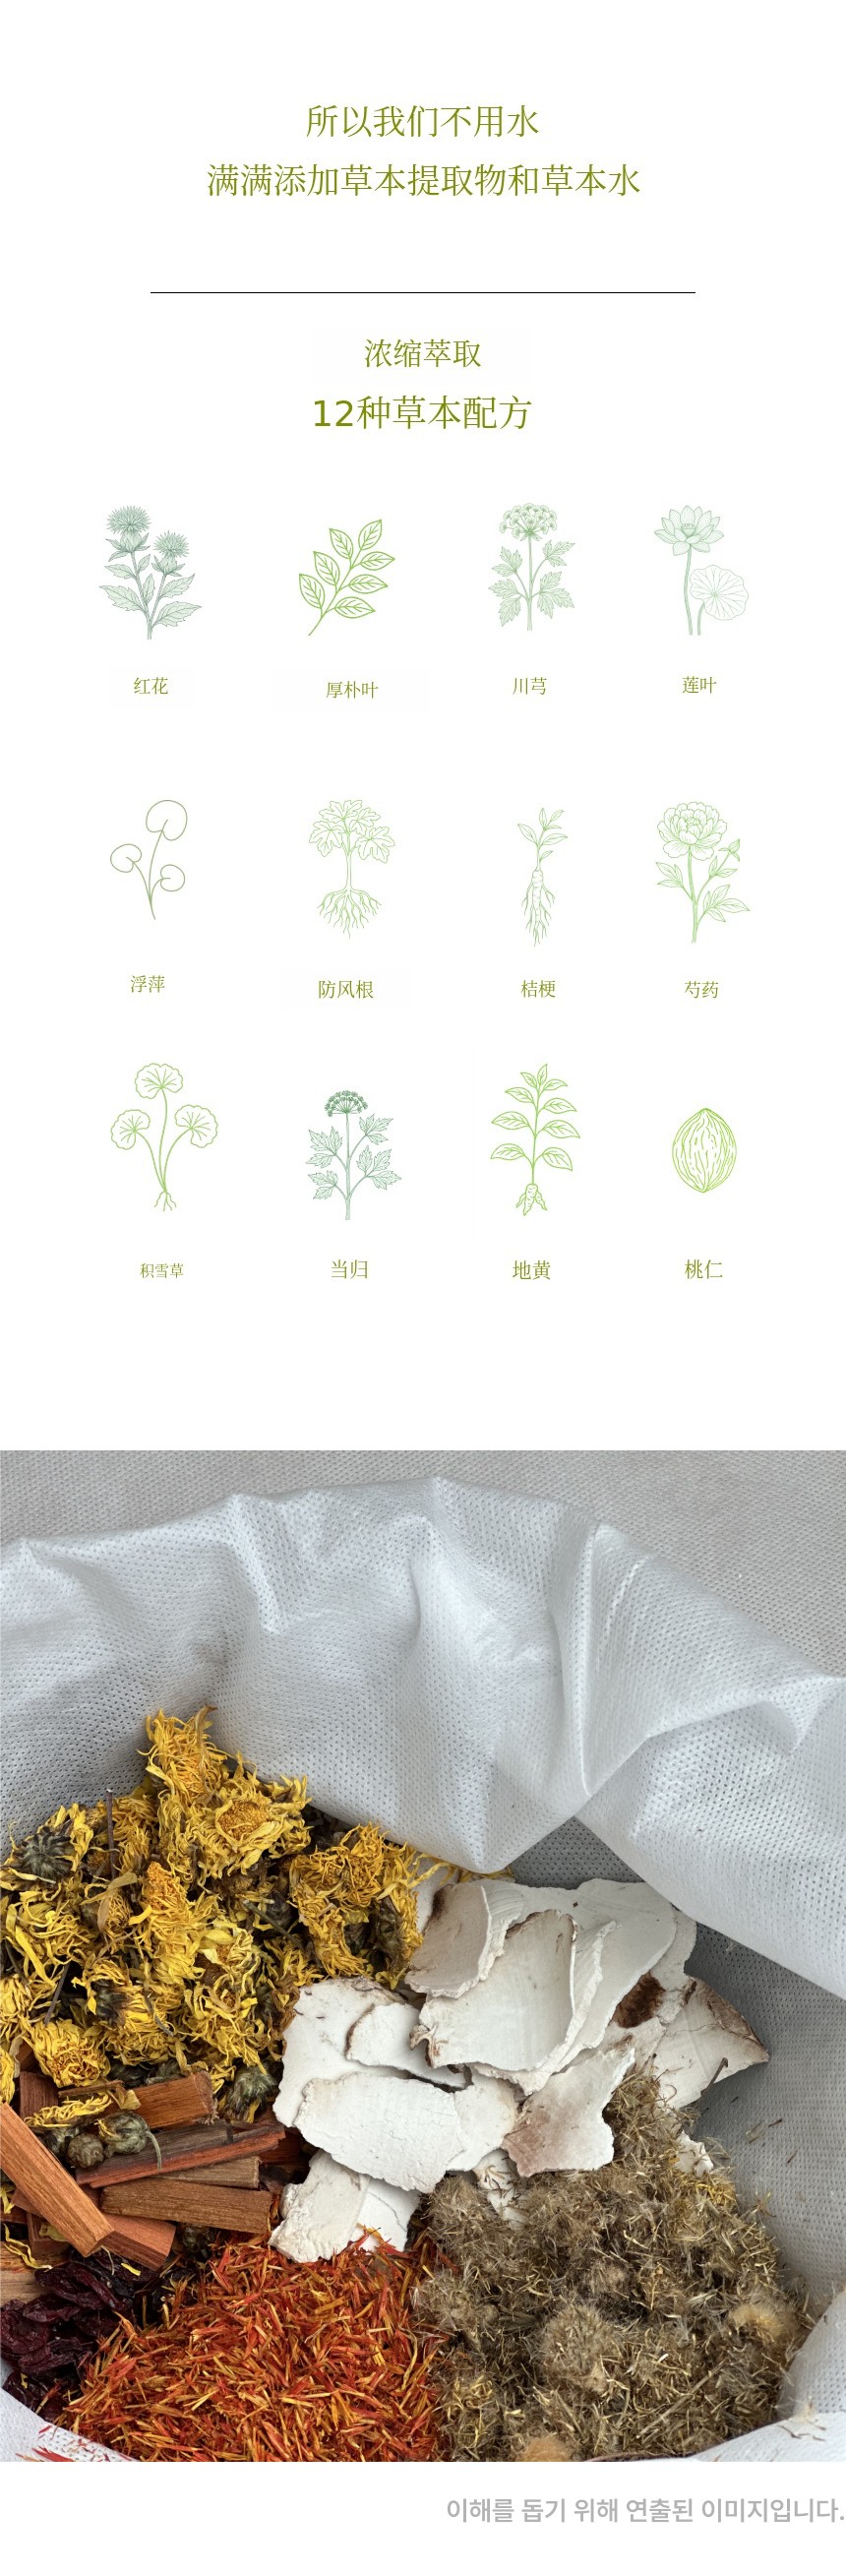

一般面霜中有28~41%是纯净水,

也就是说你知道其实就是水吗?

也就是说100ml面霜中最多有40ml只是水

本来就干燥的皮肤再喷上水

就像洗完脸后的皮肤一样

水分蒸发的同时

会变得更加干燥。

我们的草本配方非常特别!

只是把听说好的东西混合在一起用的吗?

不是的!

从400年传统的《东医宝鉴》中发现

在中医世家

代代秘密传承的配方 就是这样。